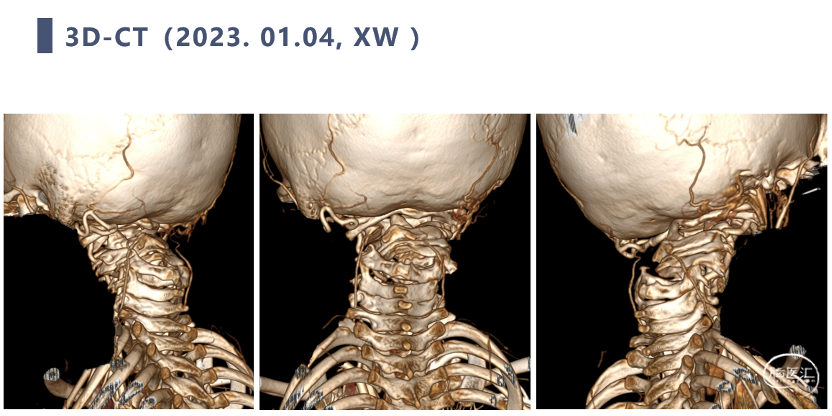

CT

牵引治疗后复查CT

CT显示颈椎椎体最大深度只有8mm,枢椎椎弓根直径3.2mm